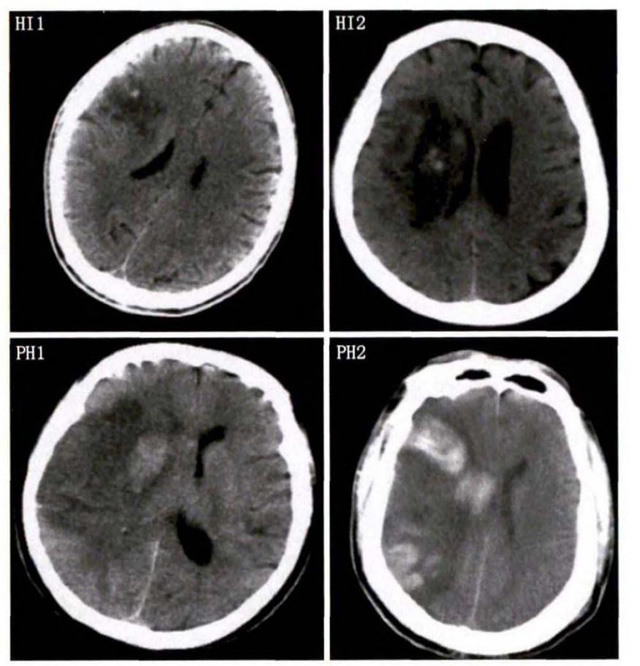

中、老年病患,有動(dòng)脈粥樣硬化及高血壓病等腦卒中的危險(xiǎn)因素,發(fā)病結(jié)合神經(jīng)系統(tǒng)癥狀和體征,應(yīng)當(dāng)考慮急性腦梗死的可能。再經(jīng)腦CT/MRI發(fā)現(xiàn)梗死灶,或排除腦出血、炎癥性疾病等,診斷即可確定。腦梗死有時(shí)頗似小量腦出血的臨床表現(xiàn)。腦栓塞在任何年齡都可以有發(fā)病的風(fēng)險(xiǎn),可以在幾秒到幾分鐘達(dá)到頂峰。會(huì)有偏癱不能說(shuō)話等局部神經(jīng)功能損壞。栓子來(lái)源很種,可能是冠心病、心肌梗塞、心內(nèi)膜炎等。合并心房纖顫,結(jié)合其他臟器官的支持診斷,CT跟磁共振都可以檢查確定栓塞位置數(shù)量還有是不是有伴發(fā)出血等問(wèn)題??梢詭椭\斷。

中老年有高血壓糖尿病發(fā)病病史,起病神經(jīng)功能缺損癥狀,臨床表現(xiàn)為腔隙綜合征,即可初步診斷本病。如果CT或磁共振證實(shí)有與神經(jīng)功能缺失一致的腦部腔隙病灶, 符合大腦半球或腦干深部的小穿通動(dòng)脈病變,即可明確診斷。少數(shù)患者隱匿起病,無(wú)明顯臨床癥狀,在影像學(xué)檢查時(shí)發(fā)現(xiàn)。